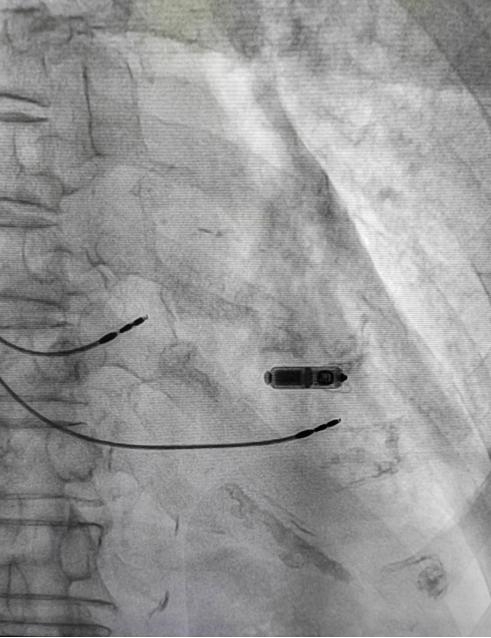

经过精心准备,干诊科/老年病科为伊大爷完成无导线双腔心脏起搏器植入。手术顺利完成,伊大爷成功拥有了“心”通路,现已康复出院,恢复到正常生活中。

相比传统起搏器植入手术,无导线起搏器植入手术具有手术时间短、无伤疤、无切口、改善患者的生存质量等优势。相较于传统起搏器,其体积减小了93%,仅有维生素胶囊大小,重量仅约2g。因此,直接植入在心腔内,患者几乎感觉不到起搏器的存在。此外,其还拥有超强的电池续航能力,寿命超过12年,同时兼容核磁共振扫描的功能,可以为心脏提供持续稳定的动能。